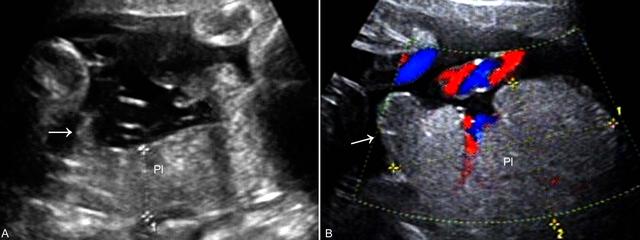

超声显像检查(2D-US)在早期妊娠和中期妊娠可以显示多叶PL和副叶PL,亦可无明显异常发现。典型的多叶PL和副叶PL多在子宫腔增大到一定程度以后显示,在羊膜腔内除显示一个主PL外还可显示一个或数个PL回声,厚度多较正常薄,表面不光滑(图2),仔细检查可以显示其与主PL之间由血管连接;有时多叶PL在位置上并无明显分离,但PL实质内显示完整的分隔回声。多数情况下多叶PL和副叶PL难以在产前得到明确诊断;彩色多普勒血流显像(CDFI)显示PL之间的血管连接有助于对多叶PL的诊断。

图2副叶胎盘声像图

需要注意分叶或副叶PL和宫颈口的关系,以排除副叶PL前置或其连接血管前置。常发生的是胎儿常规产前检查显示正常位置的PL后忽视了对多叶PL或副叶PL的观察。笔者曾遇到一例主叶PL位置正常、忽视了副叶PL前置而出现大流血的病例。应特别强调的是中晚期妊娠、观察到正常位置PL的孕妇,在进行产前2D-US时也应要求在适度充盈膀胱后进行,以便能够显示子宫下段,排除形态异常的PL前置。另外,在副PL中,PL梗死和脐带帆状附着的发生率比较高,在检查时应注意辨认。